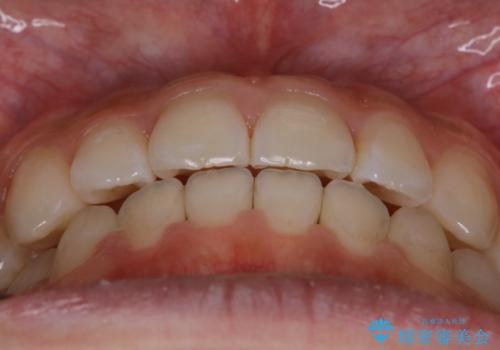

- 受け口の改善と前歯のガタつきの治療を主訴にご来院されました。

こちらの患者様の場合、上の前歯のガタつきが原因で口を閉じる際に上下の前歯の先端同士が先に当たってしまい、そこからさらに深く噛み込もうとすると下顎が前にずれていってしまうという、機能性の反対咬合であることが検査の結果わかりました。

そのため、まずは上顎の前歯のガタつきを改善していき、前歯が先に当たってしまうという症状を改善し噛み込む位置を後方の本来の位置に誘導する方法をとりました。